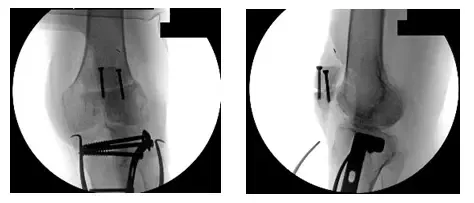

Las radiografías muestran una fijación interna por reducción abierta de la tibia y la rótula izquierdas realizada en otra institución.

Las imágenes fluoroscópicas intraoperatorias de la rodilla izquierda muestran la revisión del herraje

También se observan dos tornillos verticales en la rótula, placa lateral y tornillos transversales a través de la tibia proximal, y extracción de clavos y alambre de la rótula.